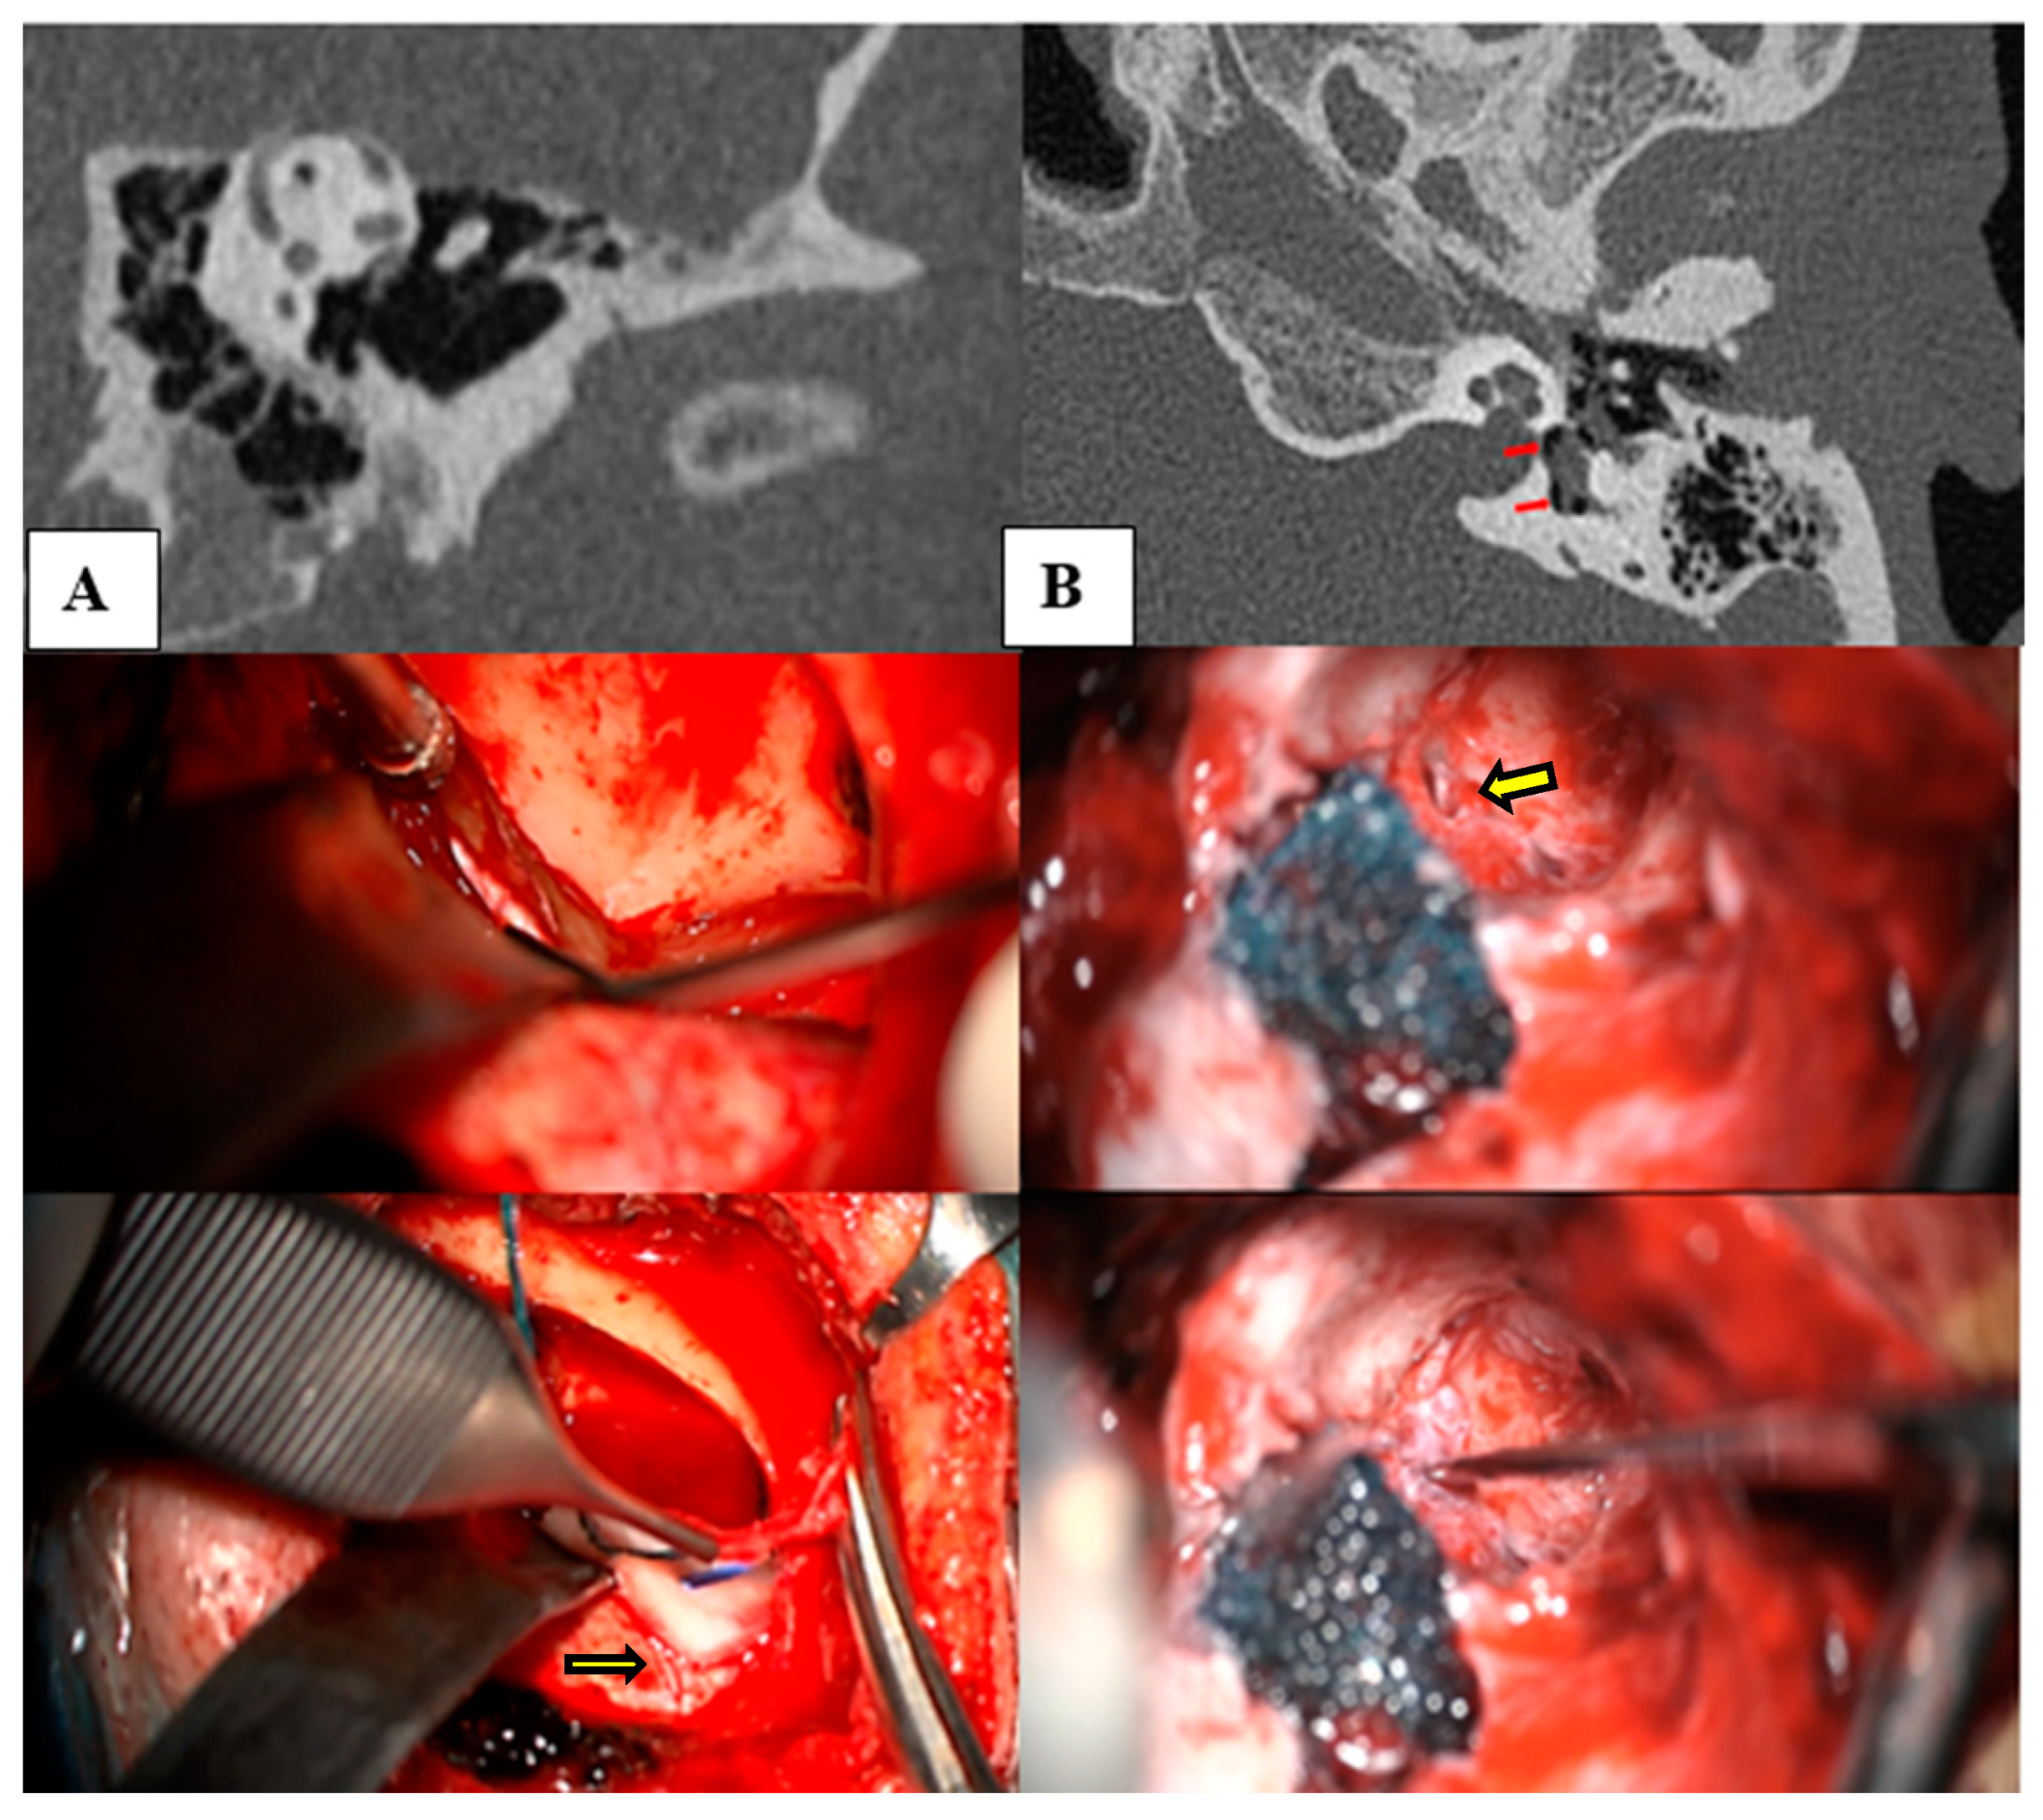

- Imaging studies: Thin-section helical CT scans (SOMATOM CT Scanner Dual Source and Single Source, Siemens Healthineers, Erlangen, Germany) with a slice thickness of 0.4 mm were employed to determine the dehiscences. To avoid selection bias and ensure rigorous criteria, only patients who presented at least one objective auditory fluctuation in pure-tone audiometry and/or those with a minimum of two episodes of spontaneous vertigo lasting longer than 20 min were selected for this test. These symptoms were used as they are considered reliable indicators of potential underlying pathologies that justify the use of advanced imaging techniques [1,8]. If these criteria were met, a 3T MRI (MAGNETOM Skyra, Siemens, Erlangen, Germany) was performed using a T2-FLAIR sequence for four hours after intravenous gadolinium administration to assess the presence of cochlear and vestibular EH.

- Wackym, P.A.; Balaban, C.D.; Zhang, P.; Siker, D.A.; Hundal, J.S. Third Window Syndrome: Surgical Management of Cochlea-Facial Nerve Dehiscence. Front. Neurol. 2019, 10, 1281. [Google Scholar] [CrossRef]

![]() Other otic capsule dehiscences | Type II Cochleo–carotid and PSC–jugular vein | 2 | 2.32% | Hearing loss: 100% Autophony: 66.67% Unsteadiness: 50% Vertigo attack: 33.33% Fullness/tinnitus: 16.67% Tullio/Hennebert: 16.67% Falls: 16.67% | 52 dB | No | No | Yes (n = 1) | Type B timpanogram with absent stapedial reflex |

| Type III Cochleo–facial and Cochleo-ICA | 2 | 2.32% | 103 dB | Yes (n = 1) | Yes (n = 1) | Yes (n = 1) | Gusher during cochlear implant | ||

| Double dehiscences (Cochleo–ICA + Cochleo–facial) and SSCD + jugular vein-EVA | 2 | 2.32% | 59 dB | Yes (n = 1) | Yes (n = 1) | Yes (n = 2) | Gusher during cochlear implant | ||